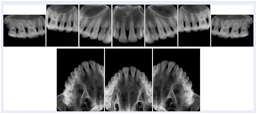

OO.1.2 Ophthalmology

1. A patient in rural Canada visits a general ophthalmologist and is found to have diabetic macular edema. The general ophthalmologist would like to discuss the case with a retina specialist before performing laser surgery. A fluorescein angiogram is done with multiple retinal images taken in a timed series after an intravenous injection. The images along with a Structured Display are shared via a Health Information Exchange with a retina specialist in Calgary, who opens them using his Ophthalmology EMR software and consults via phone with the general ophthalmologist. Both physicians view the images in the same layout so the retina specialist can provide accurate guidance for treating the patient.

2. A patient in rural Iowa visits his primary care physician for management of diabetes. Three non-mydriatic (patient's eyes are not dilated) photographs are taken of the back of each eye, and forwarded electronically along with a Structured Display to an ophthalmologist in Iowa City. The ophthalmologist reads the photos in an agreed upon layout so there is no mistake about what portion of which eye is being viewed. The ophthalmologist is able to tell the primary care physician that his patient does not need to come to Iowa City for face to face ophthalmologic care, but that there is a particular view of the left eye that should be photographed again in 6 months.

Ophthalmic Retinal Study Structured Display

Figure OO-3. Ophthalmic Retinal Study Structured Display

3. A patient in rural Minnesota experiences sudden vision loss and goes to a general ophthalmologist, who acquires OCT images and forwards them electronically along with a Structured Display to a retina specialist six travel hours away. The retina specialist is able to view the images in the standard layout that he is comfortable with, and to confirm that the patient has a choroidal neovascular membrane. He determines that is would be worthwhile for the patient to travel for treatment.